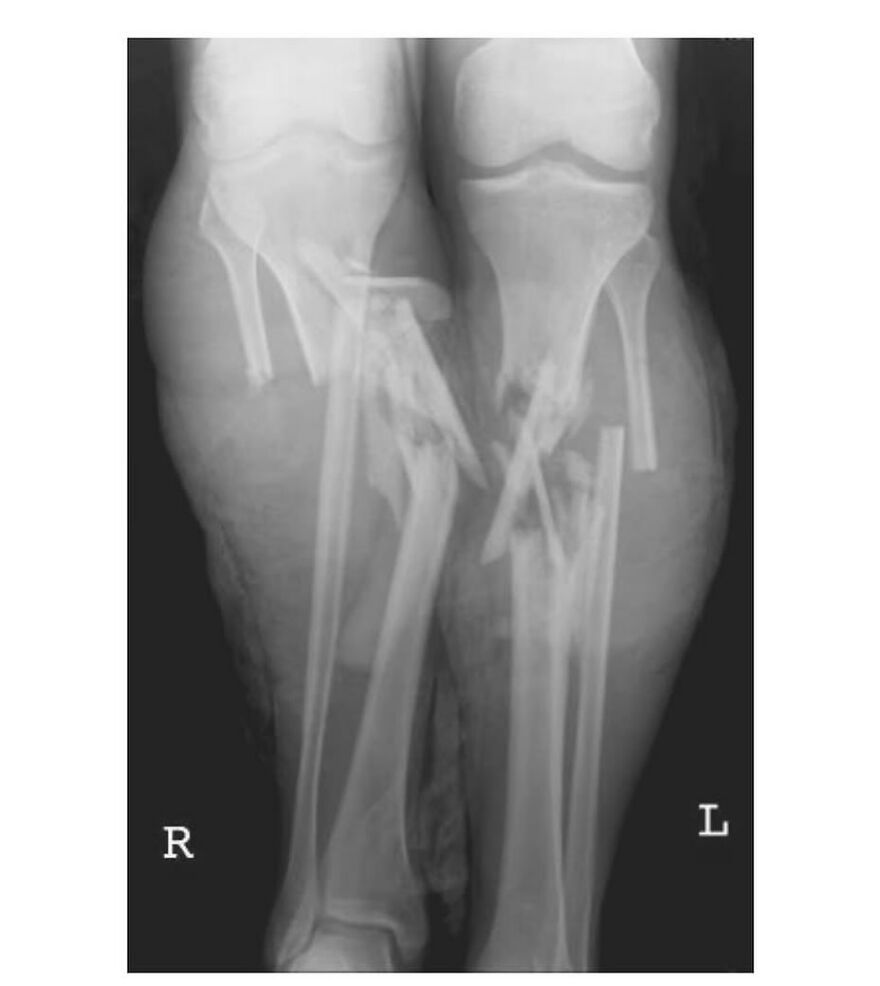

A dodgeball injury that resulted in radius and ulnar shaft fracture, aka broken forearm!

This sustained dodgeball injury has led to a bilateral diaphyseal fracture involving both the radius and ulnar shaft, thereby presenting as a fracture of the forearm.

This particular injury entails the disruptive discontinuity of the long bones situated within the antebrachial region, namely the radius and ulnar diaphyses.